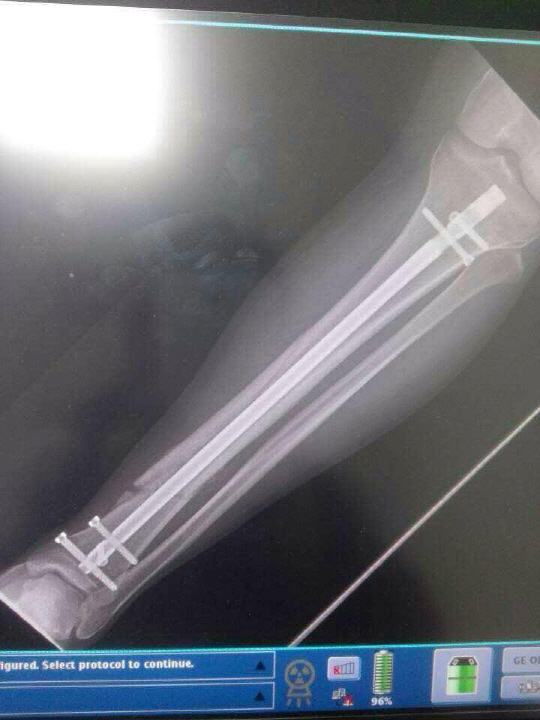

호사다마였다. 2013년 11월 경성현은 왼다리가 부러졌다. 수술을 받았다. 병원에서도 1월에나 걸을 수 있다고 했다. 철심을 박았다. 절망적었다. 하지만 경성현은 한줄기 희망의 빛에 모든 것을 걸었다. 소치동계올림픽은 2월에 열렸다. 매일 10시간 가까이 재활 훈련에 나섰다. 근육을 키워 뼈를 지탱했다. 매번 눈물이 날만큼 고된 재활훈련이었다. 기적이 찾아왔다. 다리 상태가 믿을 수 없을 정도로 빠르게 호전됐다. 1월이 되자 스키를 탈 수 있게 됐다. 소치동계올림픽에 나설 수 있게 됐다.